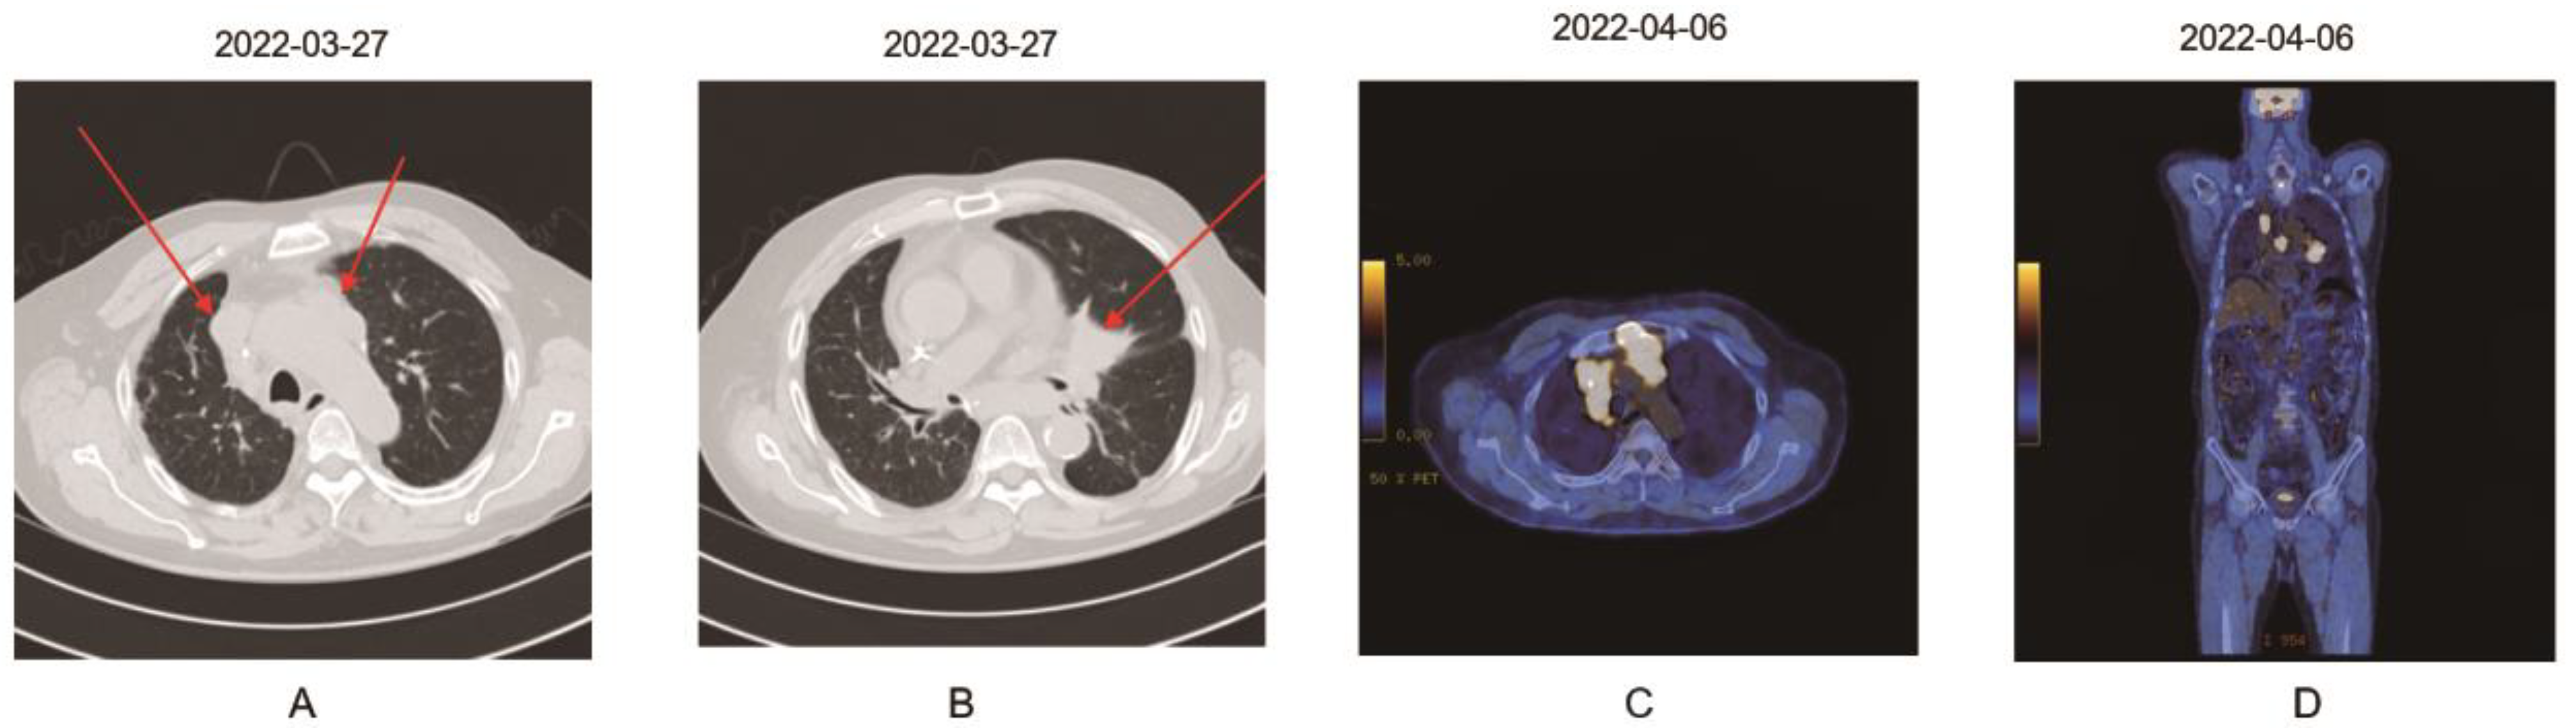

2. Case Report

| 6 | 66/male | Squamous cell carcinoma of lung (initially IIB and progressed) | Pembrolizumab (34 doses; 200 mg every 3 weeks) | CKD due to IgA nephropathy | 49 | PR | 45 | 49 | None | This report |